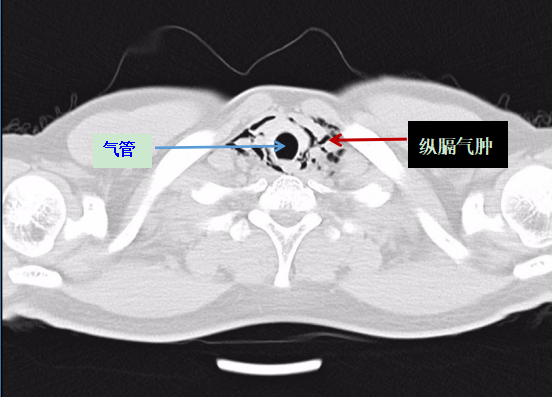

深圳市人民医院急诊科医生给阿岳做了诊察后,建议阿岳立马做一个胸部CT查看具体病情。当阿岳的胸部CT报告出来后,他立马被转到了抢救室进行治疗。

医生表示:根据胸部CT报告,阿岳被诊断为“自发性纵膈气肿”,即颈部软组织、纵隔气肿。所幸送医及时,不然后果不堪设想。

阿岳的胸部CT影像